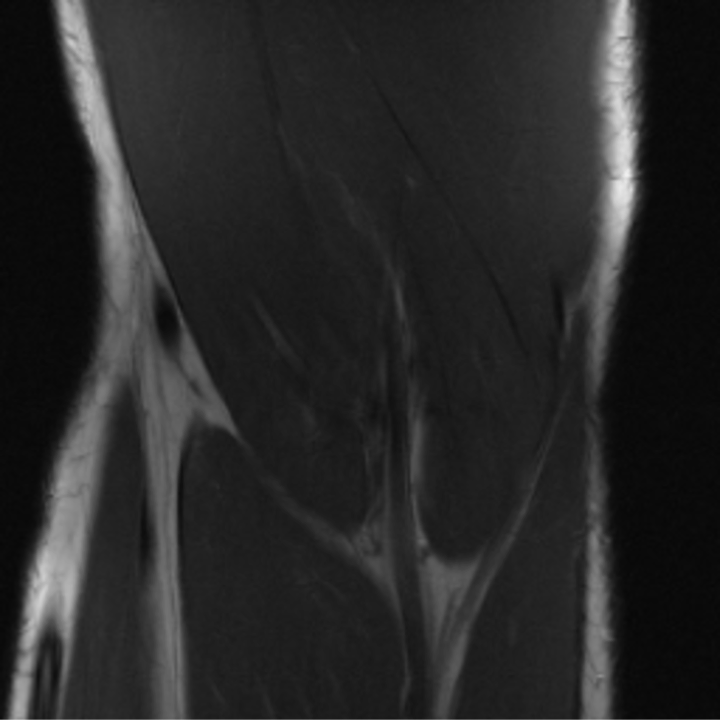

Preservation of Spine Curvature. For the spine segmentation on UK Biobank, we use a UNet++ model [83] with Dice Loss. We use a model trained to predict curves on DXA on UK Biobank [11]). We measure the Pearson correlation factor [11] of spine curvature measured on the generated MRIs where the input is a single MRI coronal slice, a single sagittal slice, or from the paired DXA, against the curvature of reference real MRIs of the same samples. The correlation coefficients are 0.89 for the coronal MRIs, 0.88 for the sagittal MRIs, and 0.87 for the DXAs on the test set of 308 human-annotated angles. We can then bin the curvature of the spines under different scoliosis categories based on human-annotated angles: mild: , moderate: , and severe . We show the results in Figure 8. This illustrates that the generated MRIs preserve the spine curvature from normal to severe scoliosis cases. Additional details about spine curvature are provided in supplementary material.

B.4 Preservation of Spine Curvature and Fat

For the spine segmentation on UK Biobank, we use a UNet++ model [83] with Dice Loss. We use a model trained to predict curves on DXA on UK Biobank [11]. We show in Figure IX that generated MRIs preserve the spine curvature from normal to severe scoliosis cases. We also study the case when DXA is used to generate the MRIs and show in Figure IX how the correlation to real curvatures compares to the input MRI case. The curvatures of the MRI generated from the coronal plane match the DXA curvatures more than the curvatures generated from sagittal MRI. This is expected since the antero-posterior plane of DXA is equivalent to the coronal plane for MRIs. This also explains the greater Pearson’s correlation coefficient of the coronal MRI (0.89) and DXA-generated curvature (0.88) compared to sagittal-generated curvature (0.87) relative to the reference curvature on the coronal plane. We observe though that MRI generation using X-Diffusion from another plane than the conventional plane for scoliosis assessment is valid.